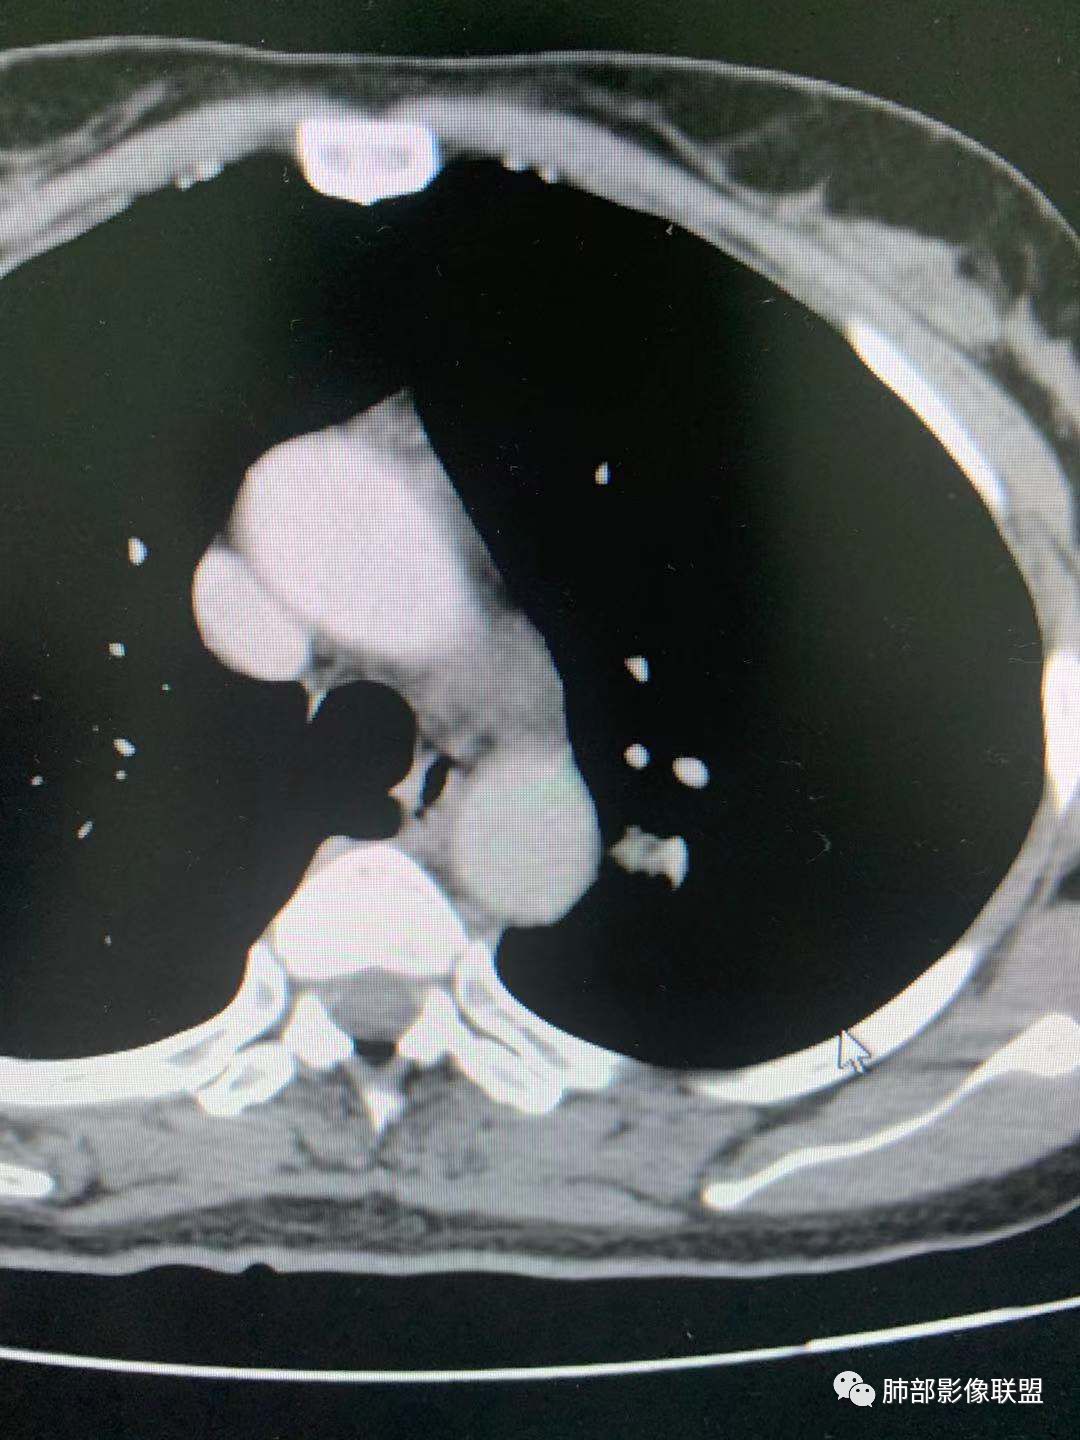

四、

这个怎么分析?

大家都考虑PSP?理由?

腺癌吧

有棘状突起,强化渐进性,强化了四十左右

导管冯

隐球菌?

凝睦

周围有边界清楚磨玻璃密度,腺癌

南边

CT值30HU;增强后:41/76HU

强化幅度:46HU

蓝天白云

周围有边界清楚磨玻璃晕

无胸膜牵拉

收缩力弱

1、边界清不清?

边缘平直,延迟强化,血管贴边,支气管推移,毛刺较软,收缩力较弱。

血管贴边

欣

大部分清,有小部分模糊

最上部层面,血管杂乱无章

增粗扭曲

2、形态规则吗?

果哣.

边缘粗毛刺

金豆

类圆形

小赵

规则

如果这样,大家下一步应该观察啥?

旁边支气管倒是好像没有明显变窄。倾向于惰性腺癌,需要与psp鉴别

与支气管关系

长毛刺

啥关系啊?

从边绕过

支气管靠外侧,无明显变窄

好像是挤压,最好做重建

图不足啊,需要补充

这两条交代清楚了

这一条?

走形自然,无变窄,无明显侵犯

堵了?还是边上走了?

没堵

堵了是如何堵的?

我想提个上图一个疑问,为啥这靠内侧支气管的管径,比外侧支气管还窄?

你看血管啊

伴行

外侧伴行的血管大啊

提示它是级别更高的支气管啊

如果支气管堵了,考虑PSP几率就很小

所以我需要补充这个的重建

看清楚这条支气管

还是有收缩力

周围GGO不均匀,边界偏清

是的,有胸膜凹陷